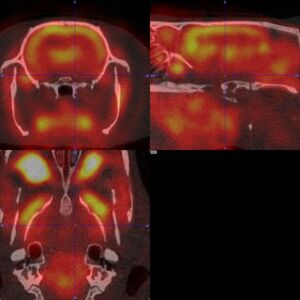

The PET/CT Si78 is a high throughput imaging instrument, dedicated for drug and tracer development for clinical translation . It combines highest PET sensitivity with fast and low dose CT.

The PET/CT Si78 is a molecular imaging system for sequential Positron Emission Tomography (PET) and X-Ray Microtomography (uCT). The fully shielded scanner, the animal welfare solutions and the experimental workflows are designed to support high throughput translational preclinical research in all field s of nuclear molecular imaging research.